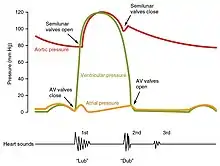

Heart sounds

The closure of the heart valves causes the heart sounds.

Typically, healthy hearts have only two audible heart sounds, called S1 and S2. The first heart sound S1, is the sound created by the closing of the atrioventricular valves during ventricular contraction and is normally described as "lub". The second heart sound, S2, is the sound of the semilunar valves closing during ventricular diastole and is described as "dub".[7] Each sound consists of two components, reflecting the slight difference in time as the two valves close.[80] S2 may split into two distinct sounds, either as a result of inspiration or different valvular or cardiac problems.[80] Additional heart sounds may also be present and these give rise to gallop rhythms. A third heart sound, S3 usually indicates an increase in ventricular blood volume. A fourth heart sound S4 is referred to as an atrial gallop and is produced by the sound of blood being forced into a stiff ventricle. The combined presence of S3 and S4 give a quadruple gallop.[7] Heart murmurs are abnormal heart sounds which can be either related to disease or benign, and there are several kinds.[81] There are normally two heart sounds, and abnormal heart sounds can either be extra sounds, or "murmurs" related to the flow of blood between the sounds. Murmurs are graded by volume, from 1 (the quietest), to 6 (the loudest), and evaluated by their relationship to the heart sounds, position in the cardiac cycle, and additional features such as their radiation to other sites, changes with a person's position, the frequency of the sound as determined by the side of the stethoscope by which they are heard, and site at which they are heard loudest.[81] Murmurs may be caused by damaged heart valves or congenital heart disease such as ventricular septal defects, or may be heard in normal hearts. A different type of sound, a pericardial friction rub can be heard in cases of pericarditis where the inflamed membranes can rub together.